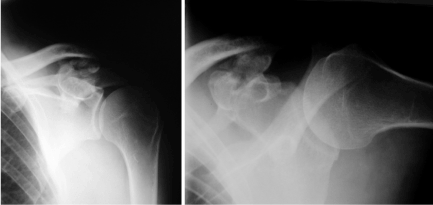

active abduction over 120°. There was local tenderness just above the left coracoid process. Radiographic examination of the left shoulder revealed the presence of a unilateral coracoclavicular joint with articular facets on the conoid tubercle of the clavicle and the superomedial surface of the coracoid process of the scapula with osteophytes, joint space narrowing and several possible loose bodies (Figure 1). The x-ray of the right shoulder showed no signs of CCJ (Figure 2). All symptoms immediately regressed after fluoroscopy guided intracapsular injection of a local anaesthetic (2 ml Xylocaine 2%) and corticosteroid (Prednisolon 10 mg). We recommended analgetic- antiphlogistic therapy (Ibuprofen 600 mg) on demand. At latest follow-up after 12 months the patient was nearly free of complaints. There was full ROM of both shoulders and slightly local tenderness just above the left coracoid process. We recommended another injection on demand and resection of the CCJ in case of recurrence if there was no sufficient pain relief after the second injection.

Figure 1. X-Ray of the left shoulder a.p. view a. and lateral view; b. shows osteoarthritis of a coracoclavicular joint with joint space narrowing, osteophytes and several loose bodies consistent (in the ap view).

Figure 2. X-Ray of the right shoulder (a.p. view): No signs of a coracoclavicular joint.